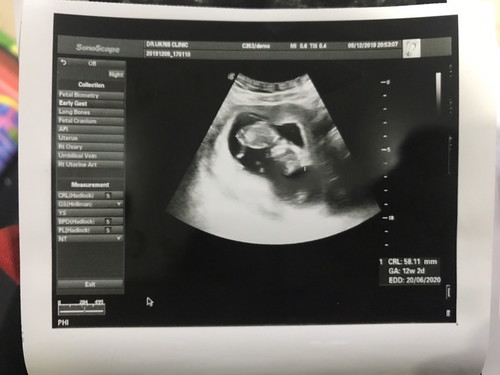

11 week ยังบอกไม่ได่ค่ะ เด็กกำลังสร้างแขน ขา อยู่ค้า ของเรารูปนี้คอน 12 week ค้า

จากภาพซาวน์ตอน13สัปดาห์ค่ะ หมอบอกเห็นชัดเลย หัว ตัว ขา แขน 😂